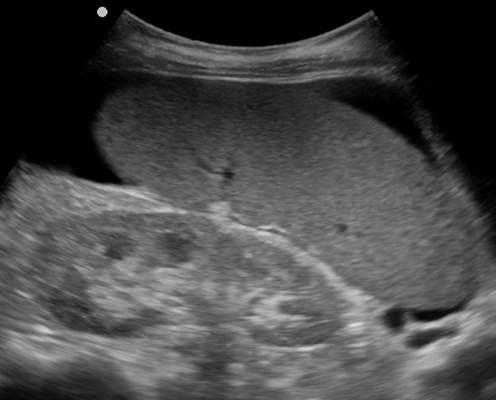

УЗИ лимфоузлов при лимфоме Ходжкина